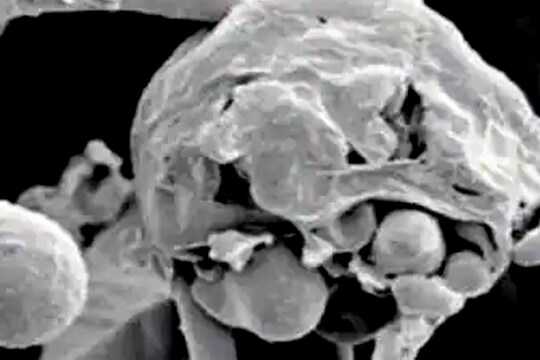

नवी दिल्ली, 27 मे : कोरोनाच्या (Coronavirus) संकटात फंगसचंही (Fungus) मोठं संकट येऊन ठेपलं आहे. ब्लॅक फंगस (Black fungus), व्हाइट फंगस (White Fungus), येलो फंगस (Yellow fungus) अशा वेगवेगळ्या फंगल इन्फेक्शनची प्रकरणं समोर येत आहेत. त्यात आता व्हाइट फंगसचं भयंकर असं प्रकरण समोर आलं आहे. या फंगसनं एका रुग्णांची अक्षरश: आतडीच पोखरून काढली आहेत. या रुग्णाच्या आतड्यांमध्ये छेद झाले (White Fungus cause hole in intestine) आहेत. व्हाइट फंगसमुळे आतड्यांमध्ये होल झालेलं हे पहिलंच प्रकरण भारतात आढळलं आहे. 49 वर्षांच्या महिलेला पोटात तीव्र वेदना होत होत्या. तिला उलटी आणि डायरियाही होता, तिला श्वास घ्यायलाही त्रास होत होता. 13 मे रोजी 2021 रोजी सर गंगाराम रुग्णालयात (Sir Ganga Ram Hospital) दाखल करण्यात आलं. त्यावेळी तिच्या तपासण्या केला आणि रिपोर्ट पाहून डॉक्टरांना धक्काच बसला. रुग्णालयाच्या सर्जिकल गॅस्ट्रोएंटरोलॉजी अँड सीवर ट्रान्सप्लांटेशन विभागाने दिलेल्या माहितीनुसार, सिटी स्कॅनमध्ये या महिलेच्या पोटात हवा आणि द्रव असल्याचं दिसलं. तिच्या आतड्यांमध्ये छेद असल्याचं हे लक्षण होतं. तिच्या अन्ननलिकेत, छोट्या आणि मोठ्या आतड्यांमध्ये छेद झाले होते. हे वाचा - अरे बापरे! तोंडाबाहेर लटकतेय जीभ; कोरोना रुग्णाला झाला भलताच साइड इफेक्ट रुग्णालयातील डॉक्टर अनिल अरोरा यांनी सांगितलं की, “रुग्णाची प्रकृती खूपच नाजूक होती. आम्ही रुग्णाच्या पोटातून जवळपास एक लीटर पस आणि बाइल लिक्विट काढलं. त्यानंतर तात्काळ तिचं ऑपरेशन करण्यात आलं. या रुग्णावर शस्त्रक्रिया करण्यात आली. तब्बल चार तास ही सर्जरी चालली. डॉक्टर समीरन नंदी यांनी सांगितलं की, “चार तास आम्ही ही आव्हानात्मक सर्जरी केली. महिलेच्या अन्ननलिका आणि आतड्यांचा छेद बंद करण्यात आला आहे. तिच्या आतड्यांतून लिक्विडता होणार स्राव थांबवला आहे. छोट्या आतड्यांना गँगरीनही झाला होता. तो भाग काढून टाकण्यात आला आहे आणि आतड्यांचा एक छोटा भाग बायोप्सीसाठी पाठवला” रुग्णालयाने दिलेल्या माहितीनुसार या रुग्णाला कोरोनाचा संसर्ग झाला होता. यानंतर रुग्णाच्या या रुग्णाची तपासणी केली असता, ही समस्या व्हाइट फंगसमुळे उद्भवल्याचं निदान झालं. हे वाचा - मानवी शरीरावर आधीपासूनच आहे अगणित फंगसचं वास्तव्य, आढळतात 80 प्रकारच्या बुरशी “आतड्यांच्या बायोप्सीमुळे आम्हाला समजलं की, तिच्या आतड्यांमध्ये व्हाइट फंगस होतं”, असं डॉ. अरोरा यांनी सांगितलं. अँटीफंगल ट्रिटमेंटनंतर रुग्णाला आराम मिळाल्याची माहितीही त्यांनी दिली.